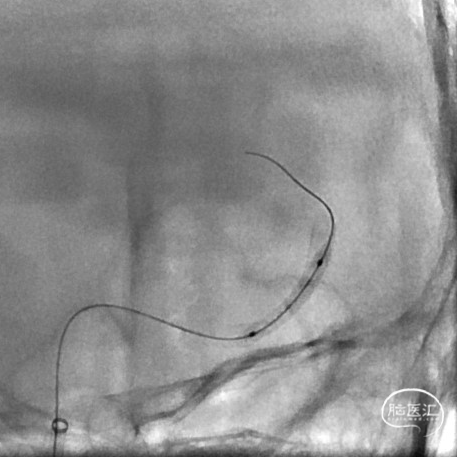

为尽快开通血管及处理动脉瘤,选择2.75*20mm 密网支架释放,并予以2.0*15mm 球囊后扩。

术后即刻影像,M2段远端血流mTICI 3级,动脉瘤内造影剂滞留。